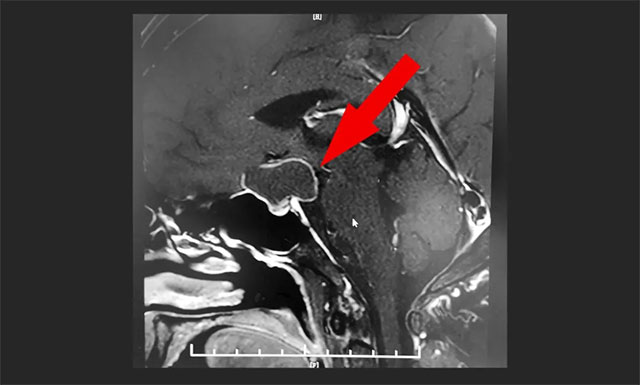

鞍区MRI平扫+增强显示,鞍上区大囊样占位,增强扫描薄壁强化,灶矢横高径约3*2*2cm;鞍上结构(下丘脑、视交叉)均受压,鞍隔下塌,鞍底腺垂体稍变扁,其左侧份强化欠均匀。

▲ MR显示鞍上区大囊样占位